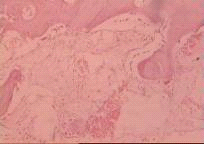

На 30 сут. эксперимента в межотломковой щели определяется зрелая фиброретикулярная ткань с меньшим количеством тканевых кист, небольшим количеством тонкостенных сосудов с единичными лимфоцитами и макрофагами, меньшим количеством по сравнению с 3 группой зрелых и незрелых костных балок. Контуры краев отломков не отчетливы. В кортикальной пластинке прослеживается увеличение по сравнению с 3 группой числа расширенных сосудистых каналов. Периостально - небольшая фиброзно-хрящевая мозоль с включением более зрелых костных балок (рис.12).

Рис.12. Образование соединительной ткани и костных трабекул в межотломковой щели. Окраска гематоксилином эозином. Увеличение х 200.